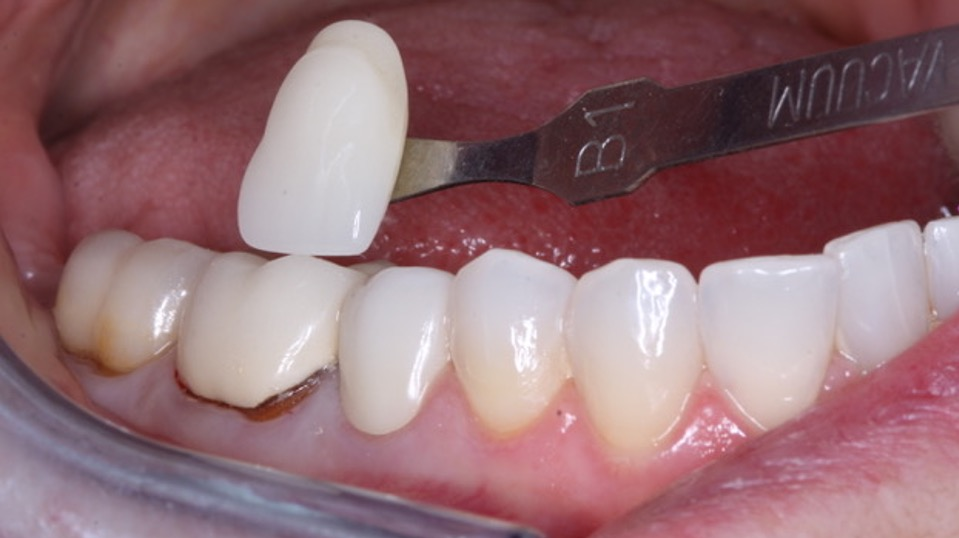

Many disinfectants have been used to kill organisms in or on tooth preparations. A few well-known ones are benzalkonium chloride, chlorhexidine, ethanol, isopropanol, peracetic acid, eugenol, and others. They disinfect to various levels of effectiveness, but most do not desensitize the tooth. Glutaraldehyde disinfects and desensitizes teeth when combined with ethylenediaminetetraacetic acid (EDTA), a wetting agent. The constituents are 5% glutaraldehyde and 35% EDTA in the commercial products. Current example products are GLUMA, MicroPrime G, Glu/Sense, and G5 Desensitizer (figure 2).